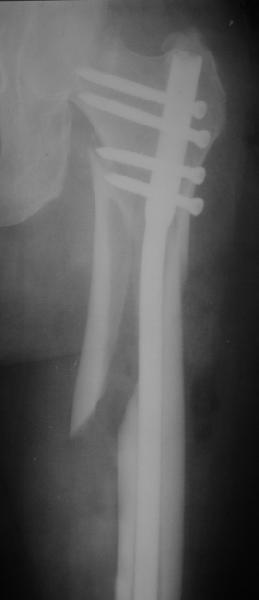

Могу скромно напомнить о существовании стержня нашей модификации.

В частности, на проксимальном конце сделано еще одно дополнительное статическое отверстие. Можно ввести в проксимальном отделе 4 винта, из них 3 статические (2 в круглые отверстия и 1 по нижнему краю овального). Картинки в приложении. На дистальном конце стержня тоже кое-что улучшено. Спрашивайте в аптеках, как говорится. Выпускается предприятием "ЦИТО" (Москва), то есть это малобюджетное решение.

Это было года 2,5 назад, мы тогда еще уточняли возможности шинирования с угловой стабильностью гвоздем с поперечным расположением винтов при переломах проксимального отдела бедра. Пациенту не пришлось приобретать намного более дорогой рекон или проксимальный гвоздь. В приложении еще несколько примеров применения того гвоздя при высоких переломах бедра, в том числе с более латеральной точкой входа. Гвоздь изгибаем для этого.